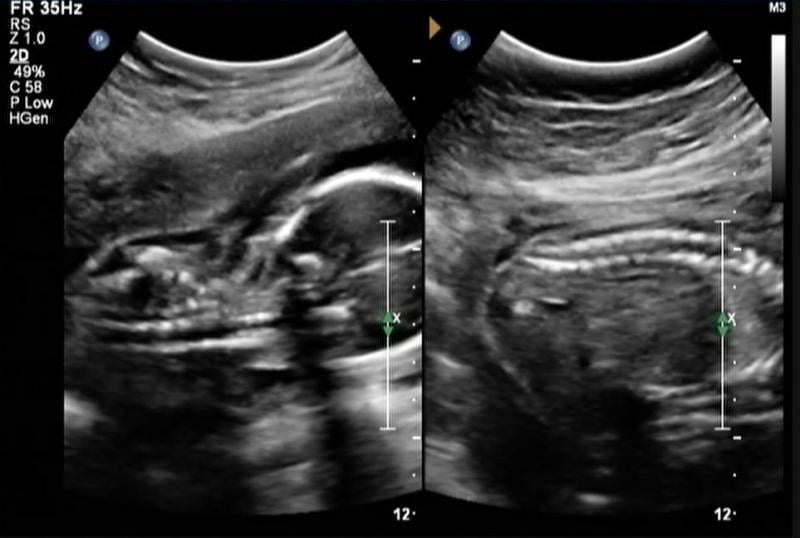

Below is a collection of prenatal ultrasound pictures from the Imaging Technology News (ITN) archive. Use the arrows to click through the image gallery. It includes transvaginal ultrasound images and fetal echocardiogram images. Fetal imaging is referred to by many names, including pregnancy sonograms, pregnancy ultrasound, endovaginal ultrasound, obstetric ultrasound, OB ultrasound, baby ultrasound, prenatal ultrasound. Fetal heart ultrasound is also called baby echo or prenatal echo.